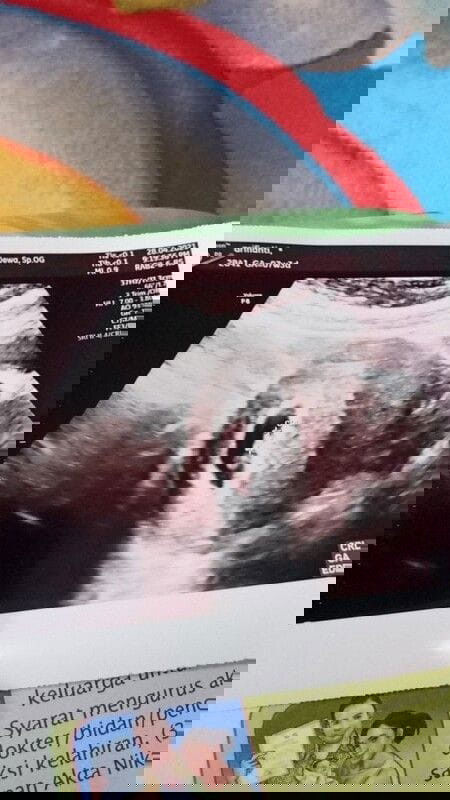

Usg Pertama di Kehamilan Pertama

masuk 7 minggu, perut sering kram .. was was bangett jd usg aja . alhamdulillah gak ada masalah di kehamilanku,.. oh ya Btw ini usg pertamaku. Masyaallah,,, aku terharu banget krna udah bisa denger detak jantungnya walaupun masih samar2 😍😍😘😘 smoga sehat slalu ya nak. smoga bunda2 dan calon debay d sni jg sehat slalu ❤